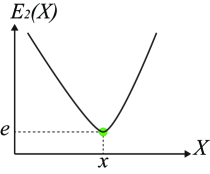

Uncertainty in object boundaries may arise from numerous sources, including graded composition (Udupa and Grevera, 2005), image acquisition artifacts, partial volume effects. Therefore, various image segmentation methods have been intentionally designed to output probabilistic or fuzzy results to better capture uncertainty in segmentation solutions (Grady, 2006; Zhang et al., 2001). Figure 6 demonstrates an example of how uncertainty information can be observed in an energy function. and in Figure 6 are two 1-D energy functions with the same optimal solution. However, segmentations near the minimal solution in have very similar energy values (high uncertainty) as opposed to solutions near the same optimal point in (less uncertainty/more certain). In fact, under the energy , a small perturbation in the image (e.g. additional noise) may change the segmentation result significantly. Given a probability distribution function over the label space, i.e. in (4), one way to calculate the uncertainty at pixel is to use Shannon’s entropy as: . The entropy can be used as an energy term in a segmentation energy function. In this case, lower entropy corresponds to larger certainty and vice versa.